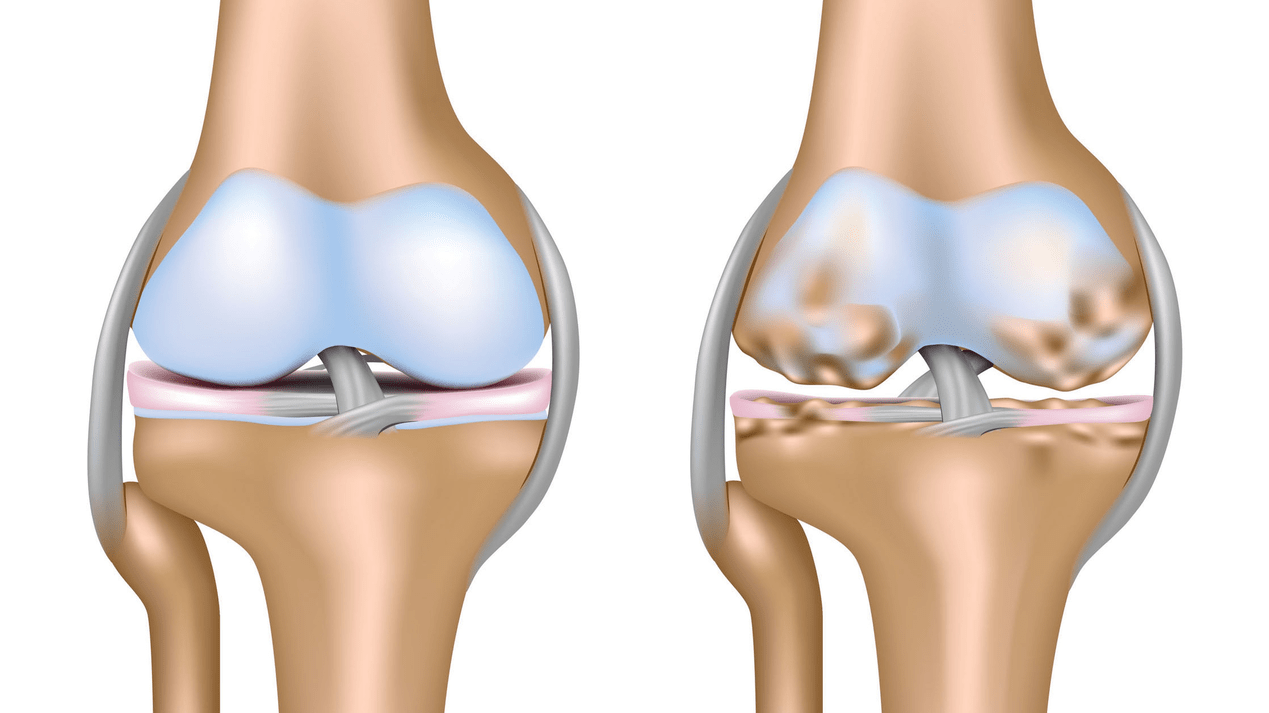

Arthrosis of the knee joint (gonarthrosis)is a progressive chronic disease of the knee joints with damage, thinning and destruction of its cartilage part (the articular surfaces of the femur and tibia), as well as damage to the subchondral bone.Research (arthroscopy and MRI) has shown that, in addition to damage to the articular cartilage, the menisci and the synovial membrane are also involved in the process.Gonarthrosis is one of the most common orthopedic pathologies.There are synonyms - osteoarthritis (OA), deforming arthrosis.The disease is an important socio-economic problem, as it is widespread and significantly impairs the quality of life of patients due to constant pain and, in addition, becomes a cause of high disability.

Until the mid-1980s, there was no single definition of the disease.It was not until 1995 that the osteoarthritis committee of the American College of Rheumatology characterized the disease as the result of mechanical and biological factors leading to an imbalance between the processes of degradation and synthesis of the extracellular matrix of articular cartilage.As a result, fiber decay and degeneration occur, cracks, osteosclerosis and compaction of the cortical layer of the subchondral bone are formed, osteophytes grow and subchondral cysts are formed.

In arthrosis (osteoarthrosis), in addition to the progressive destruction of cartilage, the loss of its elasticity and shock-absorbing properties, the bones are gradually involved in the process.When loaded, sharp edges (exostoses) appear, which are mistakenly considered "salt deposits" - in classic arthrosis, salt deposits do not occur.As arthrosis progresses, it continues to "eat" the cartilage.Then the bone is deformed, cysts form there, all the structures of the joint are affected and the leg bends.

The first stage of the disease is characterized by primary changes in the hyaline cartilage.Bone structures are not affected.Blood supply in intraosseous vessels and capillaries is impaired.The cartilage surface dries out and loses its smoothness.If the disease is accompanied by constant tense synovitis, then Baker's cyst (herniated protrusion of the joint capsule of the popliteal region) develops.After a significant load on the joint, a dull pain appears.There may be slight swelling, which disappears after rest.There is no deformation.

In the second stage, the cartilage layer thins sharply, and in some places it is completely absent.Osteophytes appear on the edges of the joint surfaces.The qualitative and quantitative characteristics of the synovial fluid of the joint change - it becomes thicker, more viscous, which leads to a deterioration of its nutritional and lubricating properties.The pain is more prolonged and intense, often there is a crunch when moving.There is mild or moderate limitation of movement and slight deformity of the joint.Taking analgesics helps relieve pain.

Absence of cartilage in most affected areas, severe sclerosis (hardening) of the bone, many osteophytes, and sharp narrowing or absence of the joint space.The pain is almost constant, the gait is impaired.Mobility is sharply limited and deformation of the joint is noticeable.NSAIDs, physical therapy and other standard methods of treating knee osteoarthritis are ineffective.